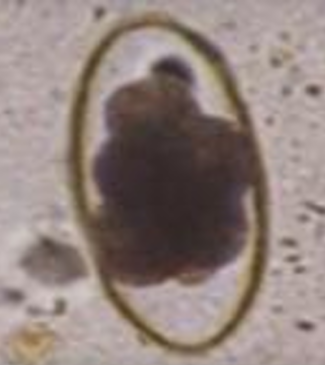

Metastrongylus spp

Ovum